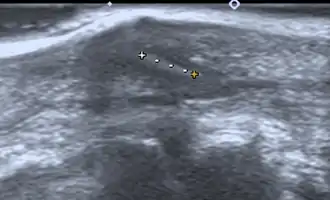

- Medical ultrasonography – used to locate glass, metal, pencil graphite, some plastics, stone, and some types of wood.[6]

Small wooden splinters (1-4 mm) distant from bones are most easily detected by ultrasonography, while CT scan and magnetic resonance imaging have higher sensitivity for those near bones.[7]